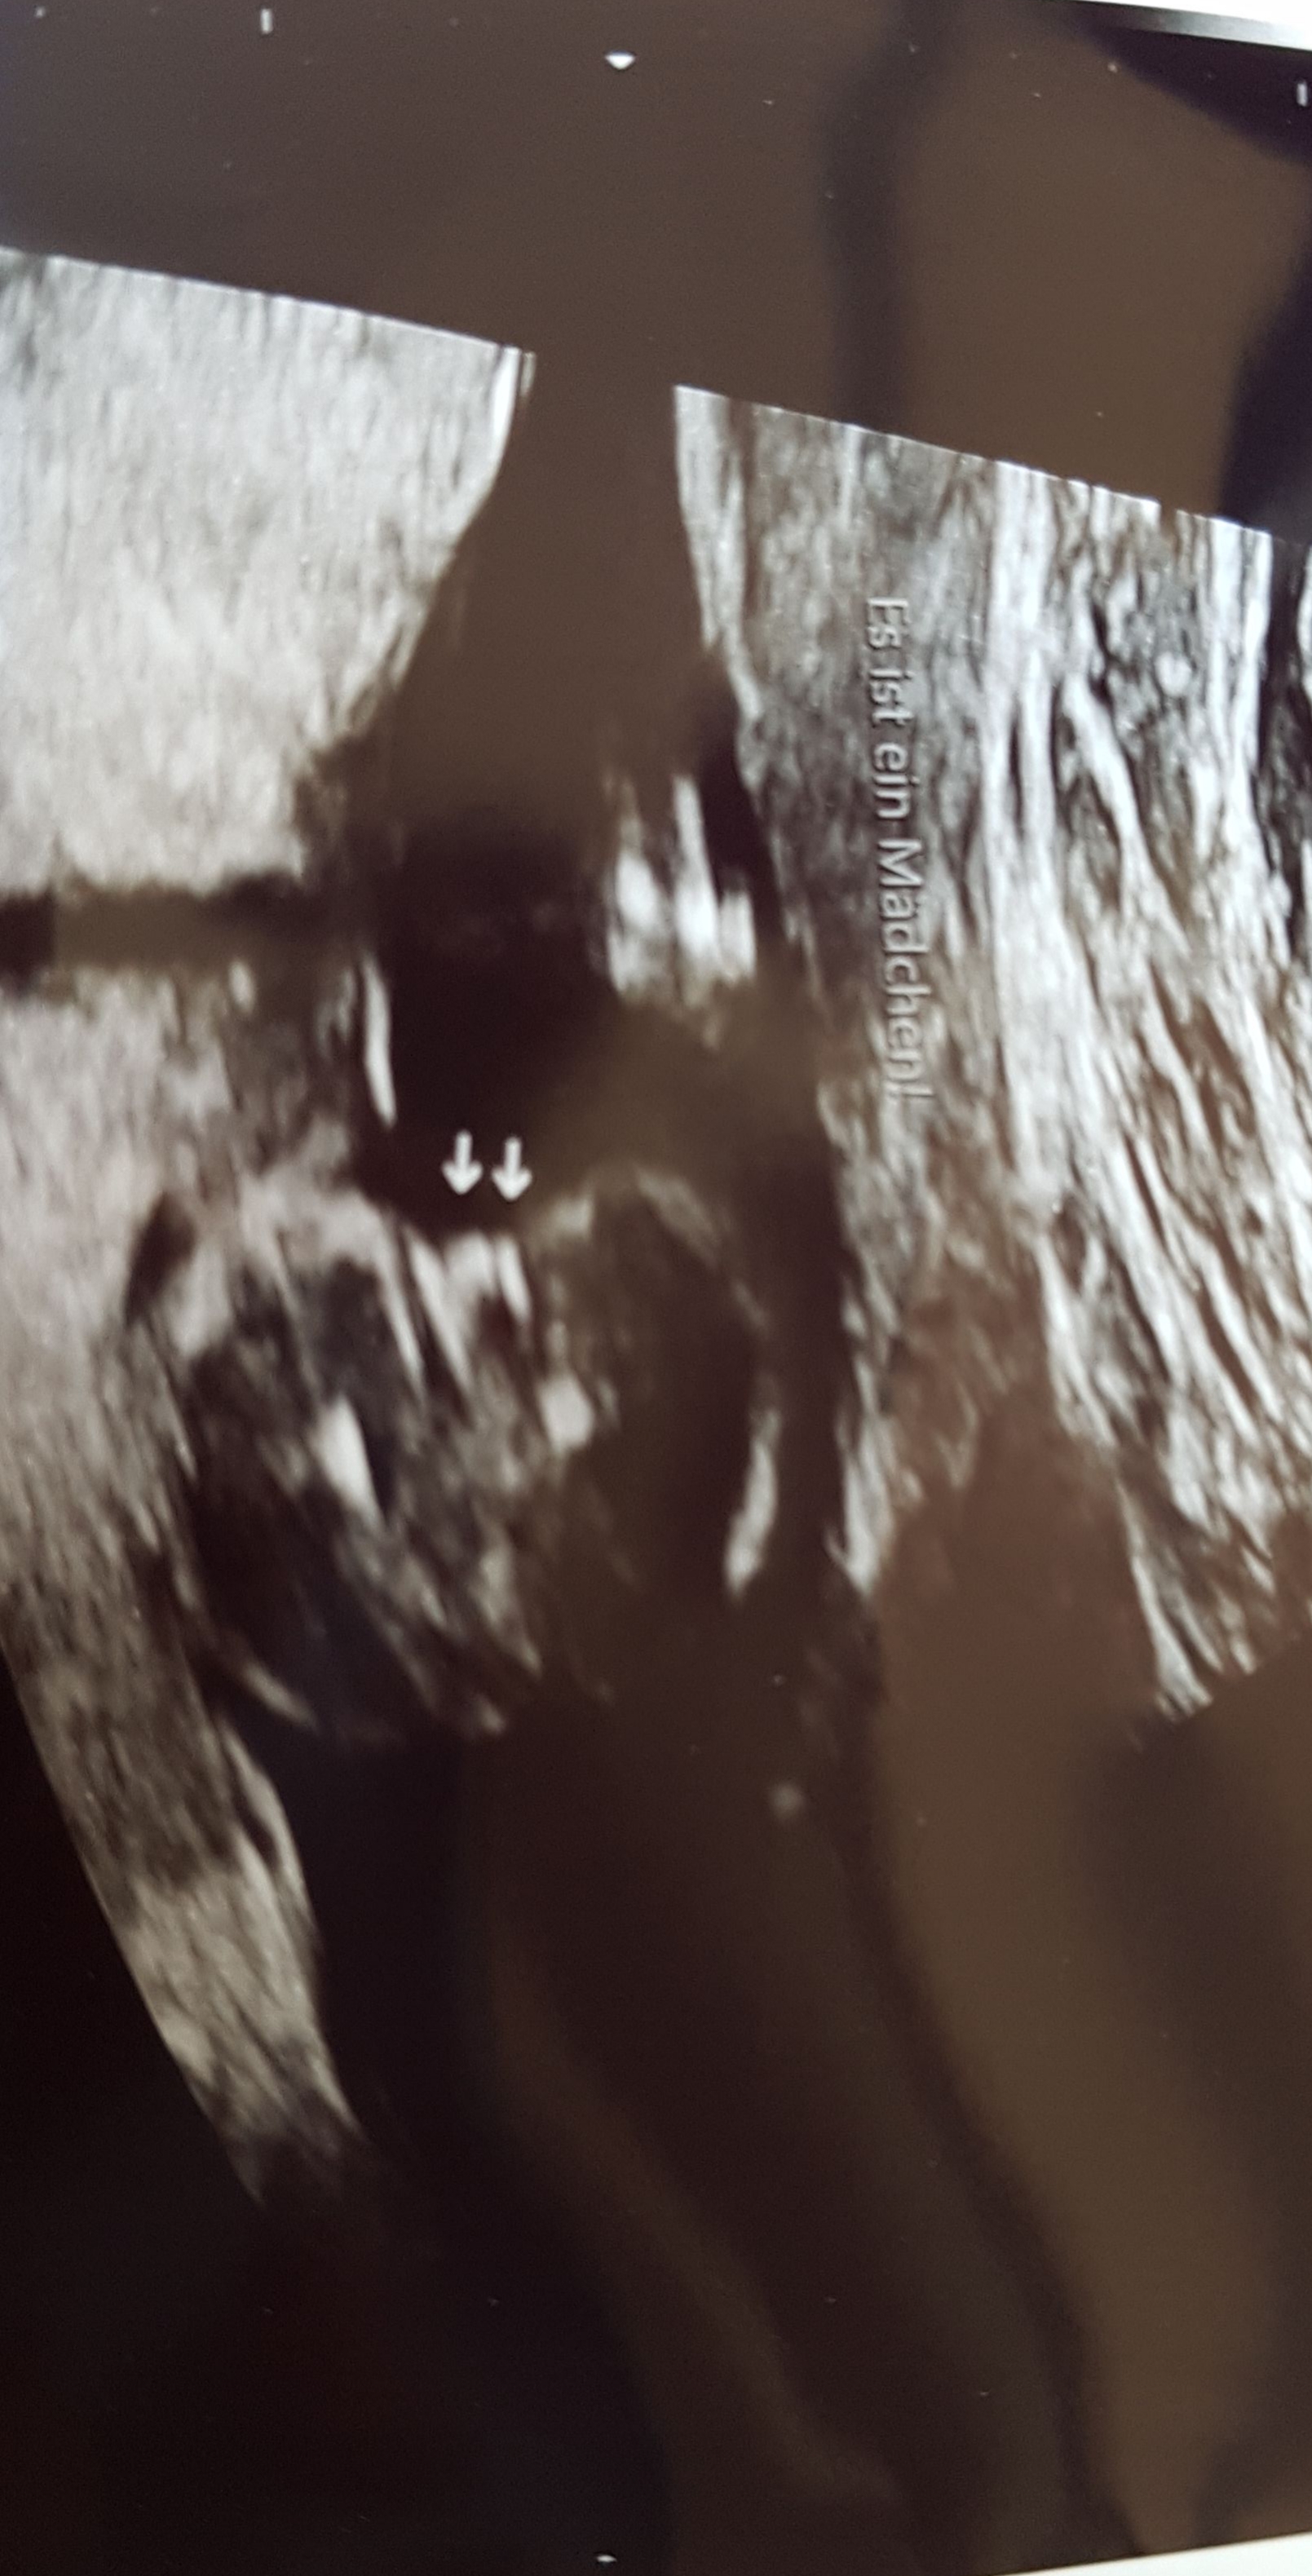

Ultraschall Das SSW 5 SSW 6 SSW 7 SSW 8 SSW 9 SSW 10 SSW 11 SSW 12 SSW 13 SSW 14 SSW 15 SSW 16 SSW 17 SSW 18 SSW 19. 15 SSW Geschlecht = Mädchen oder Junge Hallo ich bin in der 15 SSW und wahr heute beim Arzt, wegen dem Geschlecht, vor 3 Wochen hat der Arzt gesagt, es könnte ein Junge werden, weil es so aussah Jetzt heute hat der Arzt gesagt, das es wahrscheinlich ein Mädchen wird, weil man 2 Streifen (laut dem Arzt Scharmlippen) gesehen hat. In der 15 SSW bewegt Ihr Baby nun regelmäßig seine Arme, Beine und den Rest der Körpermuskulatur Der kleine Fetus kann sogar an seinem Daumen saugen Lesen Sie mehr über Sie und die Entwicklung Ihres Babys nach 15 Wochen.